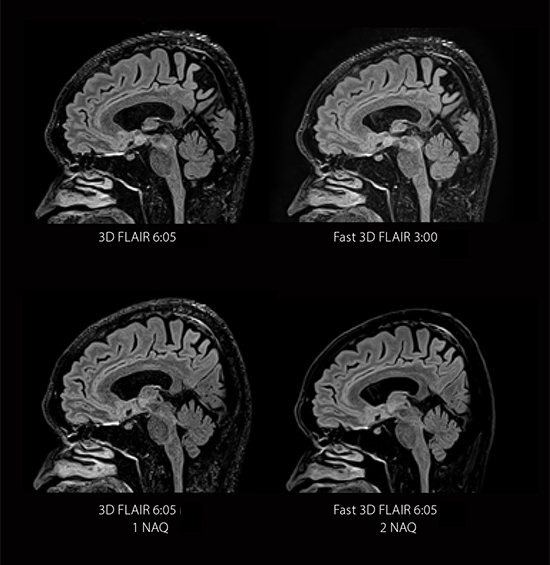

Faster Scans with Fast 3D mode

Fast 3D reduces mVox scan time by up to 50%*, allowing you to more quickly collect 3D isotropic imaging that can be reformatted into any plane.